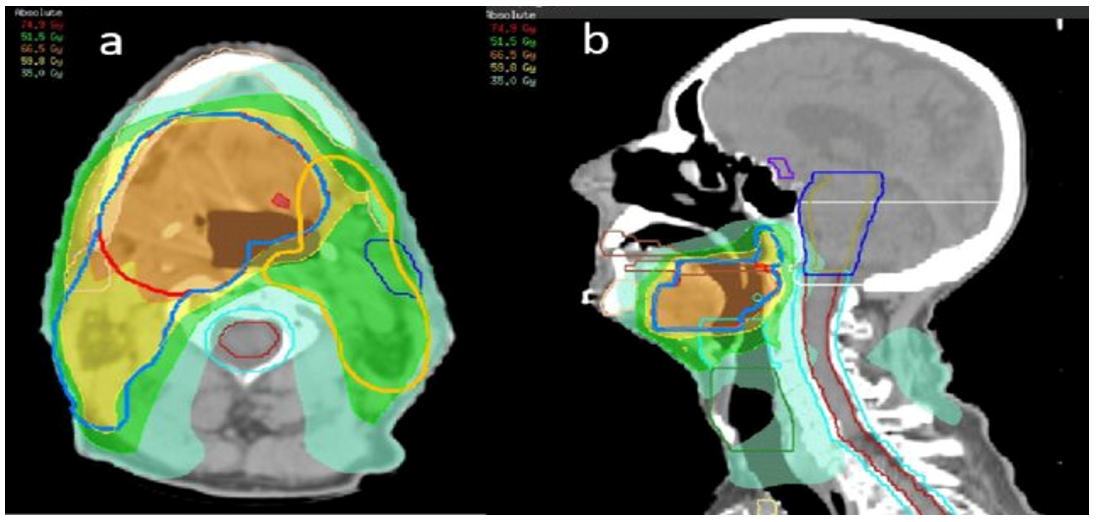

Out of 60 head and neck radiotherapy cases examined, half were treated using 3D Conformal Radiotherapy (3DCRT), and the other half received Intensity Modulated Radiation Therapy (IMRT). The analysis focused on the average dose delivered to the parotid gland, using the QUANTEC threshold of under 20 Gy as the benchmark to minimize xerostomia risk.In patients treated with 3DCRT, the mean parotid dose consistently surpassed the recommended limit, reflecting the technique’s limited ability to adequately spare the gland. On the other hand, IMRT showed markedly better dose distribution, with all cases achieving mean parotid doses below 26 Gy, several nearing the ideal target of under 20 Gy.Overall, the findings highlight IMRT’s clear dosimetric superiority over 3DCRT when it comes to protecting the parotid gland in head and neck radiotherapy (Figure 2).

Figure 2 Isodose distributions contrasting conventional (left) and IMRT (right) H&N treatment plans.

Clinical relevance of treatment approaches: Our research highlights the clinical value of utilizing advanced radiotherapy methods for treating head and neck cancers. Patients who received three-dimensional conformal radiotherapy (3DCRT) showed a greater occurrence of xerostomia, mainly because of high radiation doses to the parotid glands often surpassing 40 Gy. In comparison, intensity-modulated radiotherapy (IMRT) significantly reduced radiation exposure to the parotid glands, keeping average doses under the 20 Gy limit suggested by QUANTEC guidelines. All participants received a uniform tumor dose of 66 Gy across 33 sessions, enabling a direct evaluation of normal tissue preservation between the two methods.The inability of 3DCRT to adequately protect nearby healthy tissues further supports the advantage of IMRT in minimizing salivary gland damage. This benefit has meaningful effects on patient quality of life, particularly regarding oral comfort, eating, and speech after therapy. A meta-analysis by Marta and colleagues verified that IMRT is more effective than 3DCRT in reducing cases of grade ≥2 xerostomia among head and neck cancer patients.